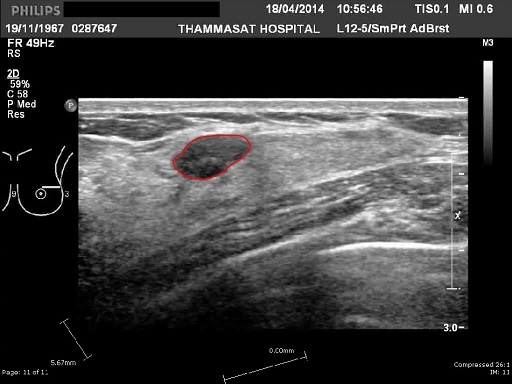

The result of the script:

Algorithm needs two coordinates to be pointed: the centre of the tumor and the point inside of it, indicating the length of the radius of the circle fiiting entirely inside of the tumor's area. Both of these coordinates are pointed by user's clicks at the beginning of each image's processing.

The accuracy of a generated contour is measured with two metrics: Sørensen–Dice coefficient and Haussdorff distance. Model contours are provided together with sample images and are also contained in the input_images folder. The report .txt file is generated by the script and contains the results of its operation. The method achieved a mean score of 82% (F1) and 10.06 (Haussdorff).